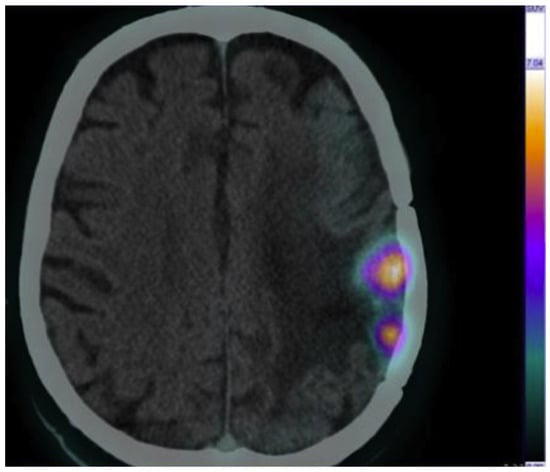

Another pilot study has been conducted by Panichelli P. et al. who evaluated the feasibility of 64CuCl2 PET/CT to image patients affected by glioblastoma (GBM) []. A high tumor uptake of 64Cu was observed in all patients affected by GBM, in contrast to the low tumor uptake of 64Cu in patients diagnosed with low-grade astrocytoma. Remarkably, in the same study, neoplastic tissue was rapidly and clearly detected with stable retention of radioactivity over time. This study provides further evidence to support using 64CuCl2 as a radiopharmaceutical for PET imaging (Figure 3).

Figure 3.

Brain 64CuCl2 PET/CT scan of a cerebral glioblastoma collected at 1 h post injection (injected activity, 13 MBq/kg). Adapted from ref. [] with permission of Panichelli P et al. Imaging of brain tumors with copper-64 chloride: Early experience and results. Cancer Biother. Radiopharm. 2016, 31, 159–167.

Similar results were obtained by Fiz F. et al., who evaluated the distribution and dosimetry of 64CuCl2 dosimetry in pediatric patients affected by diffuse high-grade glioma []. 64Cu-PET/CT presents favorable dosimetry and helps to identify tumor relapses in patients that show unclear MRI results (contrast enhancement and necrosis).